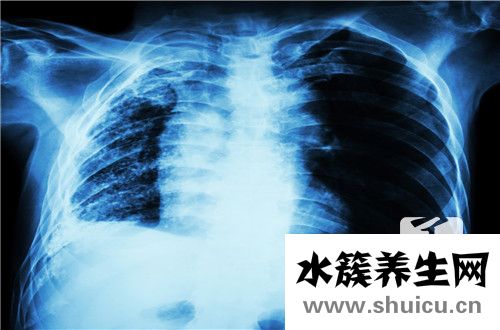

?右肺鈣化是肝實質肺細胞炎癥的陰影,通常與肝膽結石有關,并且肺血管陰影和結核鈣化的發生也可引起肺鈣化,因此應及時治療患者。 不會傳染,可以通過組織修復來改善。 對于右肺鈣化的癥狀,您可以了解以下內容。

右肺中葉鈣化灶是肝實質中肺細胞發炎后形成的瘢痕。一般來說,這不是一個大問題,一些患者可能與患有肝內膽石癥的患者具有相同的肺膨脹感。如果確診,則無需治療,右肺中葉鈣化灶可以是肺內膽管壁的部分鈣化和肺血管陰影。

鈣化是組織修復的一種手段,不需要治療,也不會傳染。一般來說,對身體沒有太大影響。在多數情況下;肺癌的鈣化斑點僅是人肝細胞壞死后的一些特殊變異。人體每天都在代謝。一些細胞壞死是正常現象。壞死后,由于肺部自身循環暢通,肺部變得平靜。在胸部X光片中形成的鈣化斑點非常像石頭的亮點。一般來說,這些斑點在胸片上僅約0.5cm。鈣化斑點,如皮膚上的長痣,只是一些壞死細胞的平靜,大多是良性,部分結核性鈣化,大多數患者本身沒有癥狀,一般不需要處理它們。

鈣化意味著當疾病治愈時,當人體組織壞死或患有腫瘤時,鈣鹽沉積在此處形成鈣化灶。在X射線或CT下,鈣化斑點通常高于骨密度,顯示出高骨密度信號。在人體衰老過程中,鈣鹽在肋軟骨沉積中的高密度影像表現,一般左右對稱密度高于骨,如果不是應該考慮病理變化。